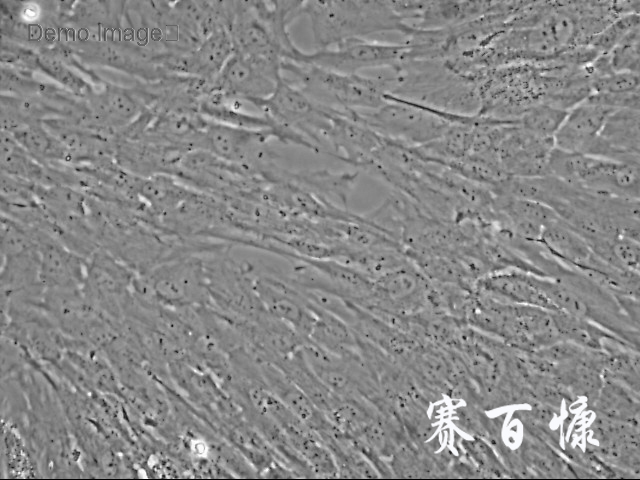

人原代输卵管平滑肌细胞

Tubal Smooth Muscle Cells

5)细胞生长方式:梭形细胞,不规则细胞,贴壁培养。